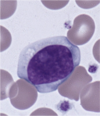

reactive "atypical" lymphocyte

28

reactive "atypical" lymphocyte

29

reactive "atypical" lymphocyte